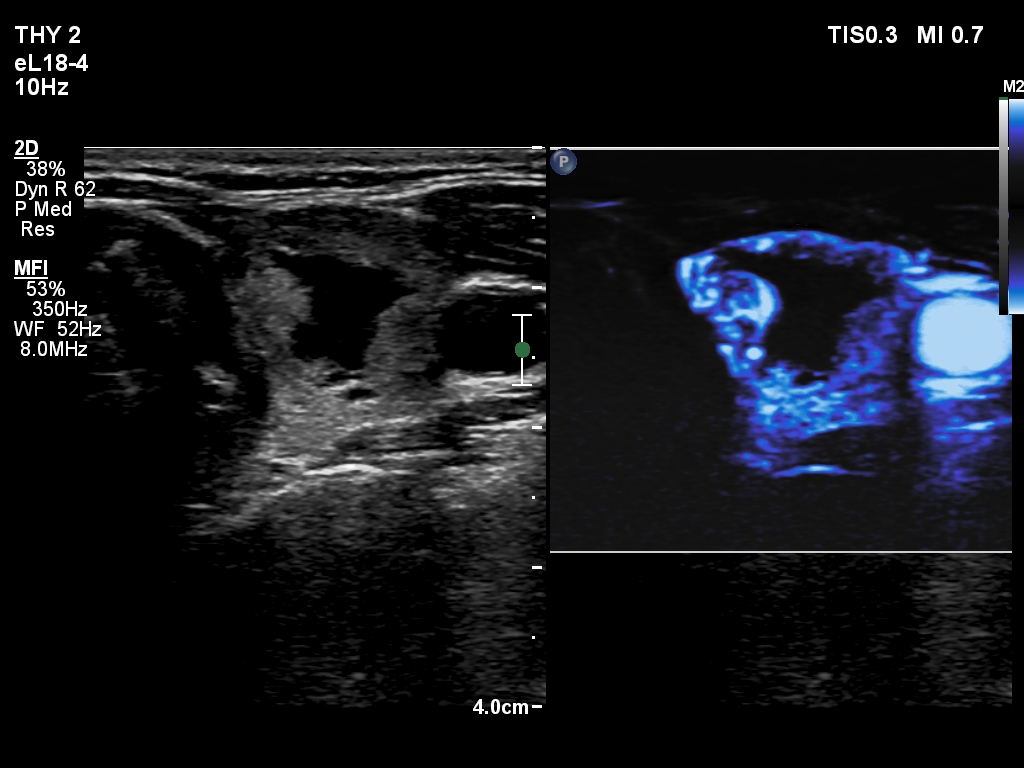

The composition of the nodule - case 2176 (ultrasonographic picture 8)

Left lobe, transverse scan, microflow imaging - after aspirating 3.5 mL brown fluid. The vessels are more easy to identify within the nodule compared with the previous situation.